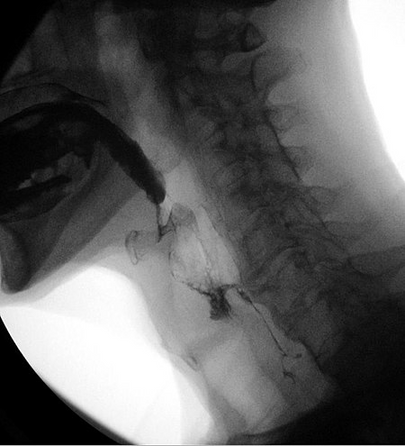

Videofloroskopik yutma çalışması (VFSS).

Modifiye baryum yutması olarak da bilinen videofloroskopik yutma çalışması (VFSS), ağız boşluğu, farenks ve servikal yemek borusunun dinamik bir röntgen muayenesidir. VFSS, yutmayı floroskopik olarak değerlendirmek için farklı kıvamlardaki sıvıların ve katıların uygulanması yoluyla bireyin yutma fonksiyonunun değerlendirilmesine izin verir.